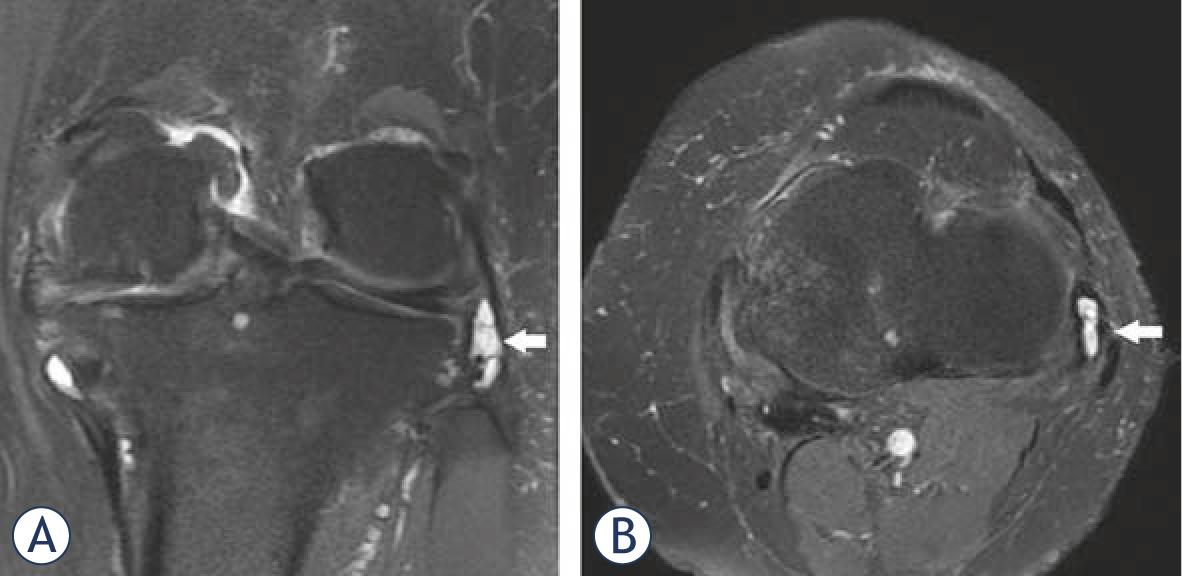

Positive correlation was present between severity of OA and CP (p = 0.03). Evaluation of lateral compartment bursae revealed lateral collateral bursitis in two patients and iliotibial bursitis in five (Figure 2 and 3). Prepatellar bursitis in the anterior compartment was determined in four patients, infrapatellar bursitis in four and suprapatellar bursitis in three. Additionally, synovial enchondromatosis was present in four patients, enchondroma in four and osteochondroma in one.

Coronal (A) and axial (B) proton-density fat-suppressed images of knee show LCL bursitis in a 70 years old patient.